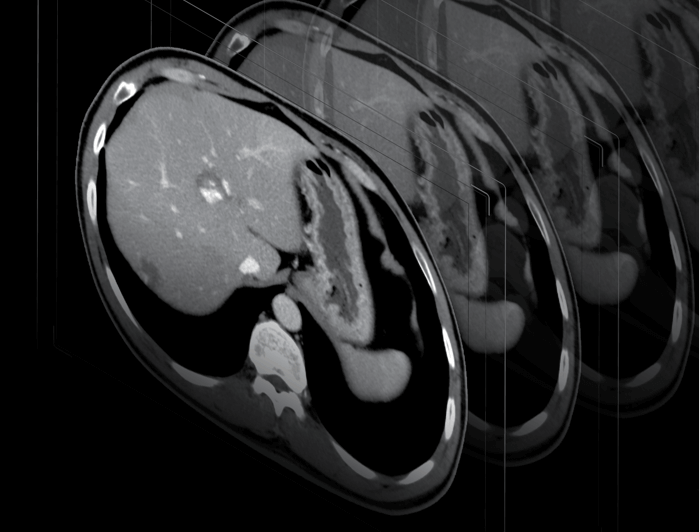

冠脉瞬时冻结技术

ePhase自由寻心精益算法

自适应冠脉对焦,有效避免搏动伪影

多扇区冠脉成像

大幅提升心脏扫描成功率